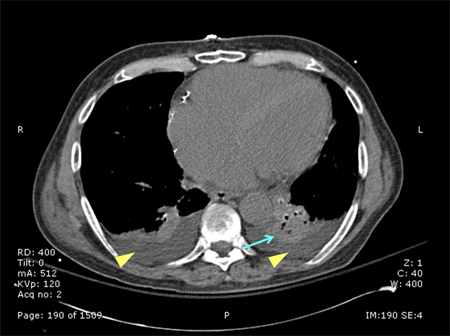

tomografia computadorizada (TC) do tórax

Uma tomografia computadorizada (TC) pode ser realizada para diagnosticar a opacidade e esclarecer se um procedimento é indicado.[Figure caption and citation for the preceding image starts]: Tomografia computadorizada mostrando opacidades bibasilares de paciente com pneumonia hospitalarConsentimento obtido na University of Louisville, Louisville, KY [Citation ends].

[Figure caption and citation for the preceding image starts]: Tomografia computadorizada de paciente com um infiltrado grande e denso no lobo inferior esquerdoConsentimento obtido na University of Louisville, Louisville, KY [Citation ends].

Resultado

pode mostrar opacidade ou esclarecer achados prévios quando a qualidade da radiografia for insatisfatória